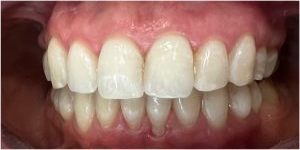

Pod kierownictwem lek. stom. Michała Badowskiego po wnikliwej analizie została przeprowadzona korekta dziąseł i pozbycie się nieestetycznych koron na podbudowie metalowej, eliminując tym samym nawracające stany zapalne dziąseł.

Następnie została wykonana wizualizacja nowego uśmiechu, idealnie dopasowana do twarzy Pacjentki. Po jej akceptacji, przygotowaliśmy komplet koron i licówek pełnoceramicznych na górne i dolne zęby.

Całe leczenie trwało zaledwie 3 miesiące!

Dzięki współpracy lek. stom. Michała Badowskiego i techn. dent. Joanny Gancarz z laboratorium Dentalscan Pacjentka zachwyca pięknym uśmiechem!